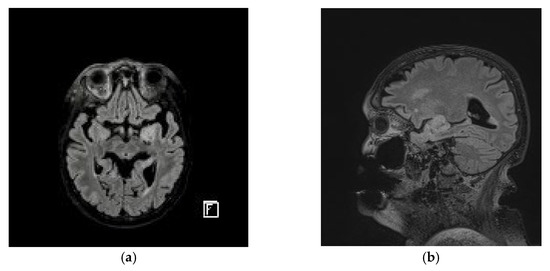

2. Case Presentation

3. Results